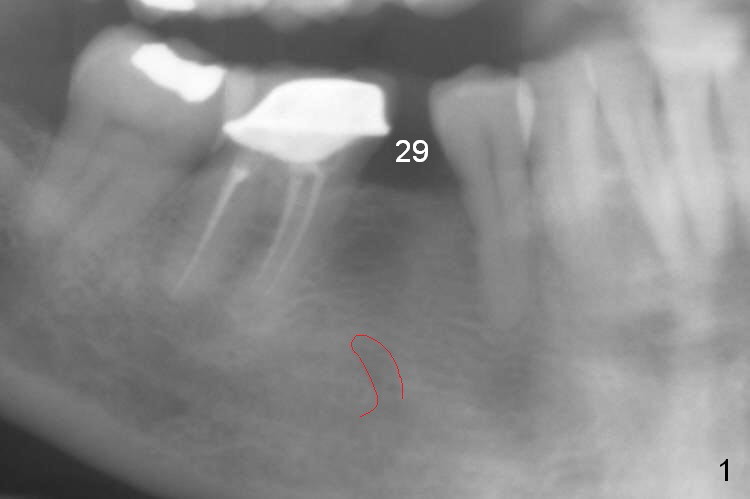

A 57-year-old woman will return for implant placement at #29, which has narrow space mesiodistally (Fig.1,2), buccolingually (Fig.3) and vertically (Fig.1, i.e., close to the Mental Loop (red outline)). Use a 2.5 or 3 mm tissue-punch from the 1-piece implant kit for access. After removal of the gingival tissue at the access, measure the tissue depth. To avoid complication associated with the narrow ridge, an incision approach appears more appropriate. The initial depth will be 12 mm using 1.2 mm drill and take PA.